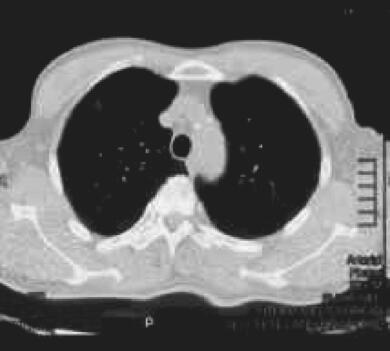

图1 2014年11月6日胸部CT

双肺多发斑片影,左肺舌段及左下肺分别可见薄壁空腔样空洞病灶,病灶周边可见晕征,右侧气胸